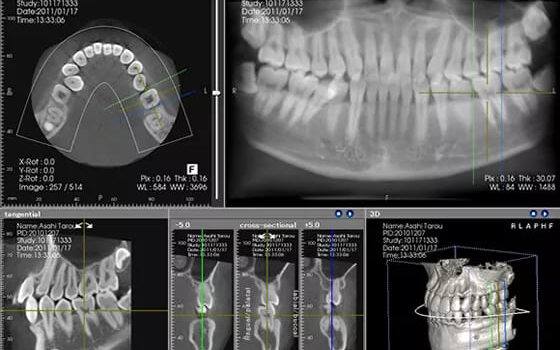

CT/レントゲン検査

歯周病は顎の骨を溶かしてしまう病気です。その進行状況を正確に把握するために、CT検査を行います。CTは3Dで立体的な画像を撮影できる装置で、歯周病の進行度を詳しく調べることができます。